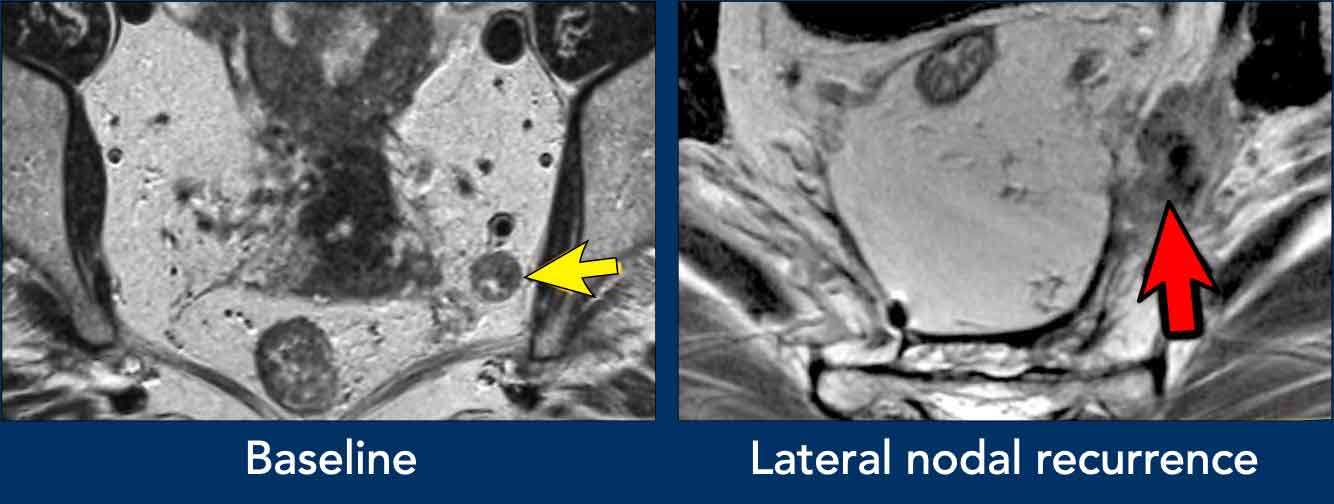

Images

• Left image: Pathologic 9 mm lymph node in the left obturator space (arrow), identified at baseline staging. Requires irradiation and/or separate resection to avoid lateral recurrence.

• Right image: Patient treated with standard TME (without lateral nodal resection) who developed an irregular mass in the left obturator space, consistent with lateral nodal recurrence.